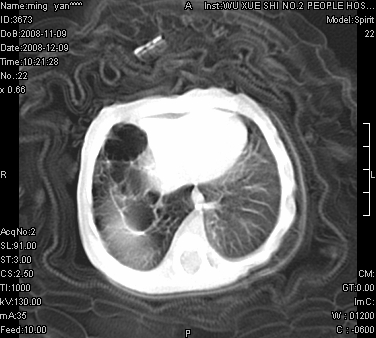

女.30天.咳嗽.喘3天.系三胞胎

考虑右肺下叶先天性肺囊肿,不除外合并右中叶肺发育不全

伴双肺感染

考虑右肺下叶先天性多发性肺囊肿可能。

考虑右肺下叶肺囊肿伴感染,右中叶节段实变或发育不全

这是一个先天性囊性腺瘤样畸形(congenital cystic adenomatid malformation,ccam),属于先天性肺发育异常,最近国外文献重新命名为先天性肺气道畸形(congenital pulmonary airway malformation,cpam),根据发生部位和畸形组织与气管、支气管的关系分成五型。本病以1岁以下婴儿多见,男性多于女性。病因为终末呼吸单元的异常增殖,形成多囊状结构。国内根据影响和病理表现分三型:ⅰ型为单个或多个大囊肿,直径大于2cm;ⅱ型为多个小囊肿,直径小于2cm;ⅲ型为大的非囊肿性病变,但显微镜下观察可见肿块由多发小囊组成(直径小于2mm)。本病可发生于肺内任何一部分,单侧肺占95%,中叶病变相对较少。